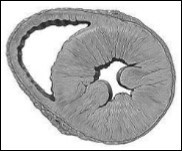

HFpEF, LV cavity typically has a normal volume and the walls are hypertrophic. See Figure 2. Histological examination shows the deposition of collagen and cardiomyocytes larger, stiffer than in HFrEF4. Despite the different cardiac structure and function, HFrEF and HFpEF hemodynamic patterns share similarities as well as differences. The clinical symptoms, renal dysfunction, neurohormonal activation, response to exercise and clinical findings may overlap10 However, increased ventricular and vascular stiffness can play a greater role than a real volume overload, in HFpEF compared with HFrEF. Thus, these two forms of IC are two well differentiated entities, with different pathophysiology and therapeutic approaches accordingly.

Figure 2.Model of concentric left ventricular hypertrophy, common in HFpEF.